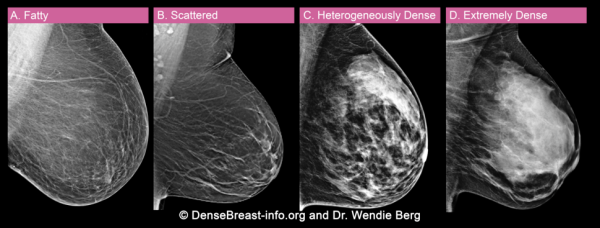

女性的乳房主要由纤维组织、腺体组织和脂肪等组织组成,在乳腺 X 线检查中,基于乳腺组织与脂肪的比例,将乳腺密度分为 4 种类型[1]:

A 类脂肪类

乳腺组织几乎均为脂肪。

B 类散在纤维腺体类

纤维腺体密度小区域性分散存在。

C 类不均匀致密类

乳腺组织呈密度不均匀致密,很有可能遮掩小肿块。

D 类极度致密类

乳腺组织非常致密,使乳腺 X 线摄影敏感度降低。

其中,C 类和 D 类统称为“致密型乳腺”。

X 线易穿过脂肪,所以分布脂肪的地方,就呈现黑色透明状;纤维腺体组织 X 线不易穿透,呈现不透过的白色。因此乳腺纤维腺体越多,白色区域则越大。如下图钼靶片所示,从 A 类到 D 类,乳腺组织致密程度逐渐增加,白色区域依次增多。